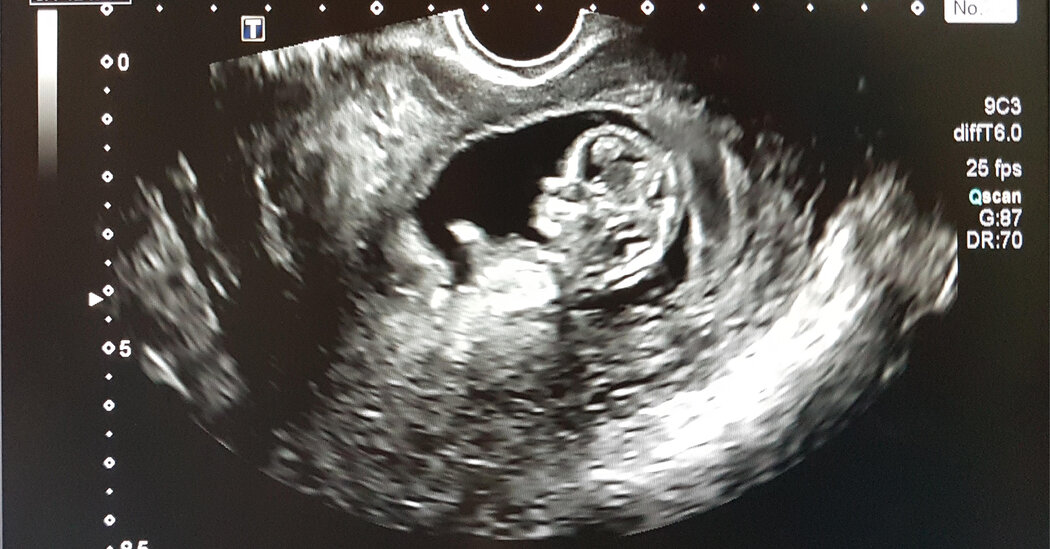

Studies suggest that morning sickness, often experienced during pregnancy, is linked to healthier pregnancy outcomes and lower risk of pregnancy loss, possibly due to higher levels of pregnancy hormones. Tips for managing nausea include eating bland foods, snacking frequently, and using ginger or supplements like vitamin B6, with professional advice recommended. The article emphasizes that morning sickness can occur at any time of day and is a sign of a developing, healthy pregnancy.